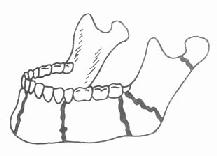

根据解剖结构上的薄弱环节,上颌骨骨折有三种经典类型(图4-12)。第一型骨折(Lefort Ⅰ型骨折)其骨折线通过梨状孔下缘、上颌窦下部,横行到双侧上颌结节;第二型骨折(LeFort Ⅱ型骨折)的骨折线通过鼻骨、泪骨、眶底、颧骨下方,达到上颌骨后壁;第三型骨折(LeFort Ⅲ型骨折)的骨折线也通过鼻骨、泪骨,但横过眶窝及颧骨上方,向后到上颌骨后壁,使上颌骨、颧骨与颅骨完全分离,因此又称为颅面分离。下颌骨是头部唯一能活动的骨骼,在解剖结构上也有它的薄弱部位,如正中颏部、颏孔部、下颌角部及髁状突颈部,这些都是下颌骨骨折的好发部位(图4-13)。下颌骨由于其突出的位置与解剖形态,是颌面部骨折中发生率最高的骨骼。

图4-13下颌骨骨折好发部位